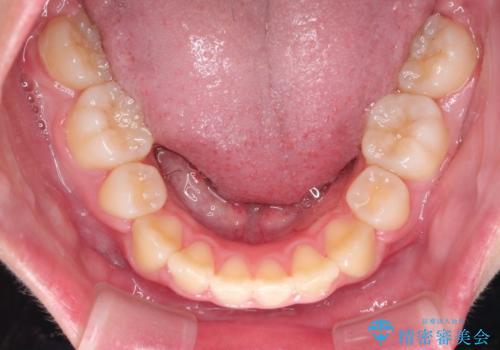

- 上下左右4本の小臼歯を抜歯、ラビアル・ワイヤー矯正を計画した。

抜歯をして第1小臼歯分のスペースを獲得することにより、ガタつきの改善と前歯のリトラクトをおこない、横顔の印象もすっきりとし、整ったEラインを作ることができました。